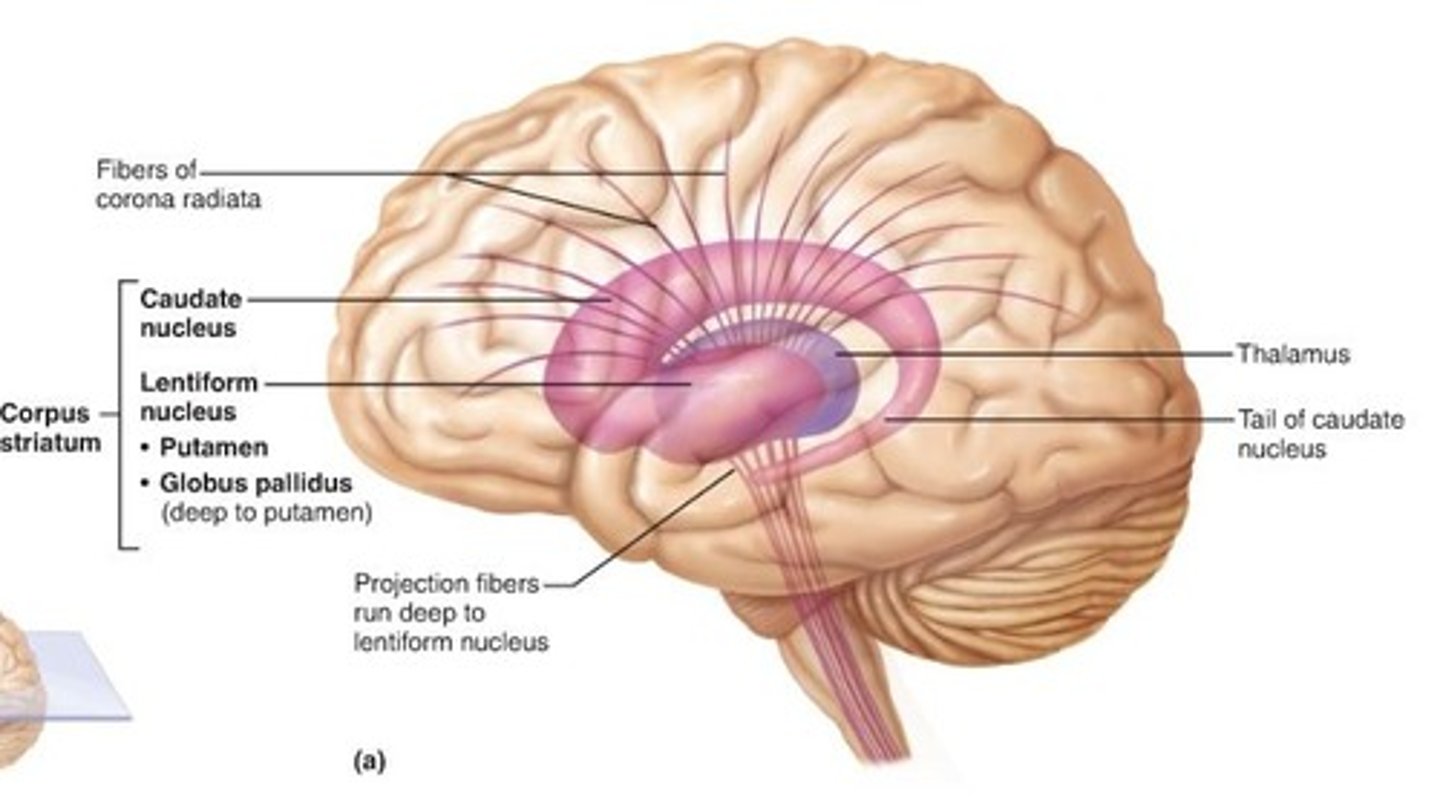

Basal Nuclei

Internal islands of gray matter dispersed bilaterally in the inferior cerebrum, diencephalon, and midbrain,

Not noted as distinct anatomical structures but functional areas,

Important in controlling and modifying motor functions

Basal Nuclei clinical: Parkinson's Disease

Results from degeneration of dopamine-releasing neurons, which causes the deprive basal nuclei they target to become overactive and produce the well-known symptoms of tremors at rest,

Cause still unknown, but may be environmental